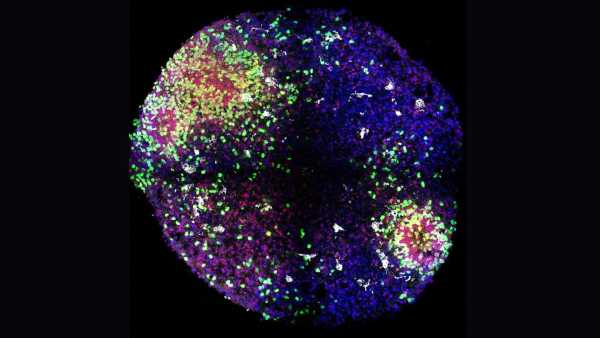

Підказки з'являються в результаті досліджень на тваринах. У дослідженні, опублікованому в жовтні в журналі Brain Research, одна група молодих дорослих мишей вільно бігала на колесах протягом чотирьох тижнів, тоді як інші залишалися малорухливими. Потім вчені виділили позаклітинні везикули — молекулярні «пакети», що несуть білки та генетичний матеріал — з крові бігунів і ввели їх малорухливим мишам.

Після того, як ці ін'єкції отримували двічі на тиждень протягом чотирьох тижнів, у цих оброблених малорухливих мишей виростило приблизно на 50% більше нових клітин мозку в області, пов'язаній з пам'яттю, яка називається гіпокампом, порівняно з необробленими малорухливими мишами. Більшість нових клітин розвинулися в зрілі нейрони, процес, відомий як нейрогенез. (Щодо людей, точаться дебати щодо того, чи відбувається нейрогенез у значних кількостях у дорослому мозку.)

Перший автор дослідження Меган Конноллі, постдокторант з Університету Альберти, розповіла Live Science в електронному листі, що її вразила специфічність ефекту — везикули, виділені з мишей, що бігають, стимулювали ріст нейронів, тоді як ті, що були виділені з малорухливих тварин, — ні. Дослідники ще не знають, чи везикули потрапляли в мозок, чи діяли опосередковано через інші сигнали організму. Але Конноллі пояснила, що самі везикули несли багато білків, пов'язаних з антиоксидантним захистом та нейрогенезом.